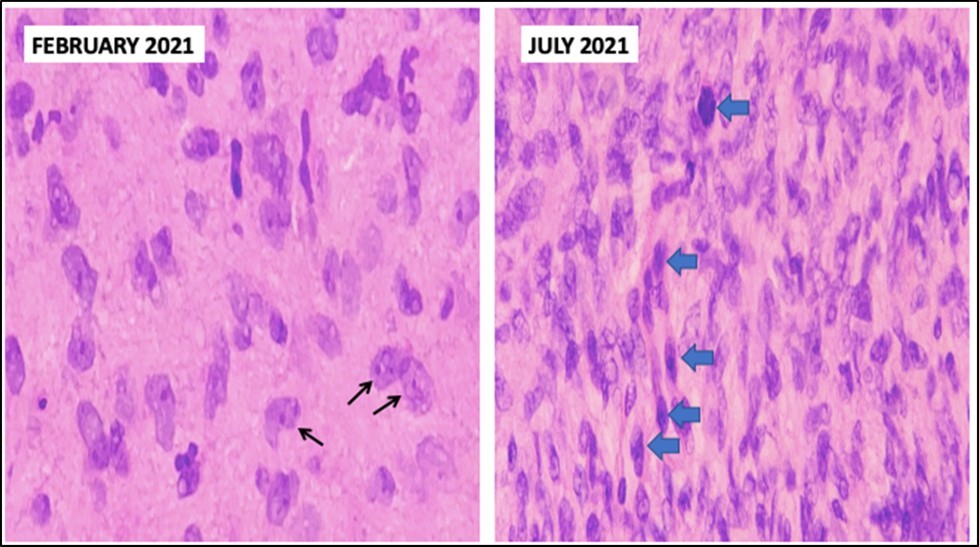

We have a case whose diagnosis needs to be confirmed. The previous biopsy showed histopathology consistent with a neurofibroma, with monomorphic, spindle-shaped, distinct cells, well-spaced, with scant mitosis. Neurofibromas are an autosomal dominant hereditary disease with a varied phenotype that affects the skin and nervous system. Affectation is one out of every 3,500 live births throughout the world. A spontaneous mutation on chromosome 17 is thought to be responsible for around half of the cases7. Figure 3. Comparison between biopsies taken five months apart. The histopathology in the biopsy done in February shows well-spaced uniform cells (black arrows). The biopsy done in July shows cellular congestion with atypical, pleomorphic cells with increased mitotic activity (blue arrows). In the most recent procedure, routine histopathology showed a different picture with higher mitotic figures and cellular congestion. The increased mitotic activity causes cellular production at a greater rate that the resulting cells show atypia and ill-defined borders. Hemorrhage and necrosis are also evident, hinting the tumor growth exceeds its vascular supply. The rapid clinical growth supported the high proliferative nature of the tumor. A diagnosis of Spindle cell sarcoma was made, with low to intermediate grade; however, a final diagnosis cannot be made based on morphology alone. To determine the type of malignancy, a panel of immunohistochemical stains was ordered. Table 1. Immunohistochemical Stain Marker S-100 Tumors of Mesenchymal origin (Sarcomas) SMA Myoepithelial cells Desmin Sarcoma vs Neurofibroma CD34 Epithelioid Sarcoma vs Dermatofibroma CK Tumors of Epithelial origin (Carcinomas) EMA Adenocarcinoma Three screening stains were ordered to identify the origin of the malignancy. S- 100 is a screening stain that becomes positive when exposed to mesenchymal cells. CK screens for malignancies of epithelial origin, while CD34 screens for hematopoietic involvement. Smooth Muscle Actin is a stain used to determine the presence of myoepithelial cells. This was chosen to consider the possibility of pulmonary metastasis. Desmin is a stain chosen due to its ability to differentiate rhabdomyosarcomas from other mesenchymal malignancies. Finally, EMA is a marker used to confirm carcinomatous lesions8 . Since the gross appearance of the tumor closely resembled muscular tissue, the S-100 stain was done first. The stain clearly showed a positive reaction. There was a note of mitotic activity in up to 7/10 high power fields with associated necrosis. This clinched the diagnosis as a mesenchymal tumor, allowing us to rule out three stains – CD34, CK, and EMA, along with their respective differentials of hematopoietic and epithelial tumors9. The initial positive reaction to S-100 allowed a narrowing of differentials to mesenchymal cell origin tumors. We could consider neurofibromas, schwannomas, malignant peripheral nerve sheath tumors, as well as metastatic myoepithelial cells. To help us differentiate, we take a closer look at SMA next. The sample did not stain to SMA, producing a negative result. This effectively ruled out myoepithelial tumors such as metastatic pleuropulmonary tumors, narrowing our differentials to neuronal tumors and smooth muscle rhabdomyosarcomas10. It was decided that determining desmin content would allow us to further narrow the differentials by differentiating between a rhabdomyosarcoma that would stain positively for desmin, and neuronal tumors such as a neurofibroma will be negative staining11,12 The specimen is composed of pleomorphic spindle cells forming sheets with a marbling pattern. Mitotic activity is present in up to 7/10 high power fields with associated crowding and necrosis. This portion of the lesion shows immunoreactivity for S100, while the remainder of the lesion has focal reactivity. Negative stains include SMA and Desmin. Since a neurofibroma can undergo malignant transformation, these last two lesions are what remain among our differentials. While morphologic histologic findings are more consistent with malignant growth, a closer look at the staining characteristics of S-100 can differentiate between the two lesions. In neurofibrosarcomas or malignant peripheral nerve sheath tumors, S100 staining is patchy and focal, with less than 50% of the specimen showing reactivity to staining. In neurofibromas, the S100 reaction is strong and diffuse, staining nearly the entire specimen13. The morphologic changes, immunohistochemical staining, and character of staining of S100 allows us to clinch the diagnosis of a Malignant Peripheral Nerve Sheath Tumor arising from a recurrent neurofibroma. Figure 4. Immunohistochemistry Staining results. S-100 shows selective staining of the cells of interest (black arrows). SMA and desmin showed negative staining of cells. In two population-based investigations, the lifetime probability of developing MPNST in NF1 patients was estimated to be 8-16 percent. Malignant transformation can begin as early as childhood, although it is most common in life's third to fourth decades. The probability of sarcoma-specific mortality is greatest in high-grade MPNST. Overall survival after five years ranges from 20% to 50%, with unresectable or metastatic cancer having a particularly poor prognosis14. Figure 5, Figure 6

Figure 3.Comparison between biopsies taken five months apart. The histopathology in the biopsy done in February shows well-spaced uniform cells (black arrows). The biopsy done in July shows cellular congestion with atypical, pleomorphic cells with increased mitotic activity (blue arrows).